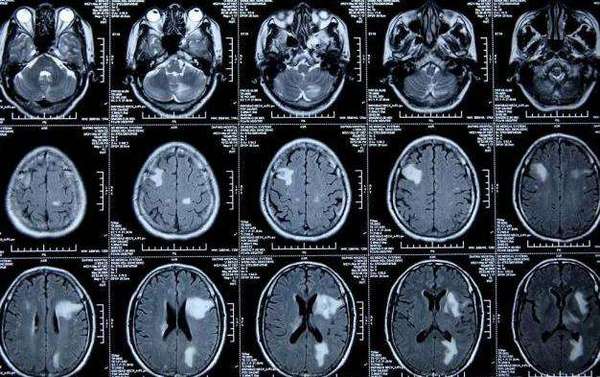

脑转移瘤mdt病例分享肺癌多发脑转移

图片尺寸1080x776